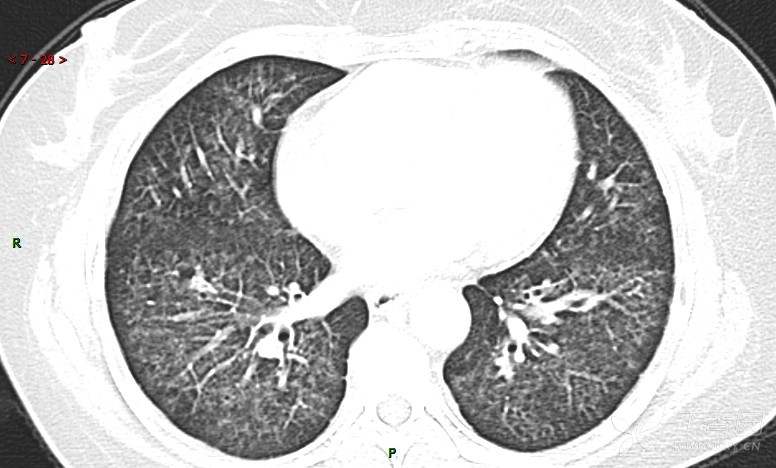

肺内弥漫性网状结节影,PET-CT却无阳性病灶,这是?(附其他2例链接)

女性,58岁,阵发性咳嗽2月,加重1月。

患者于2月前无明显诱因出现咳嗽,以阵发性干咳为主,接触冷空气后咳嗽明显,偶咳少量白色泡沫样痰,咳嗽剧烈时感憋喘,无发热、盗汗,无头痛、头晕,无胸痛、咯血,无恶心、呕吐,无腹痛、腹泻,无尿频、尿痛等不适,于当地医院给予肌注及静脉药物治疗,具体药物名称不详,效果欠佳,近1月来患者咳嗽频率较前增加,咳嗽剧烈时感双侧季肋区疼痛不适,10余天前出现发热,体温在38℃左右,伴畏寒、寒战,无头痛、头晕,无纳差、乏力等不适,药物治疗后体温降至正常,仍阵发性咳嗽,今为求进一步诊治,就诊于我院急诊,因呼吸内科暂无床位,急诊门诊以“肺间质病变”收入急诊留观室,给予“抗感染、止咳”等对症支持治疗后,今日以“肺间质性病变”收入我科,患者自本次发病以来,神志清,精神可,饮食尚可,睡眠一般,大小便正常,体重较前无明显变化。

患者活检肺组织后行PET/CT检查